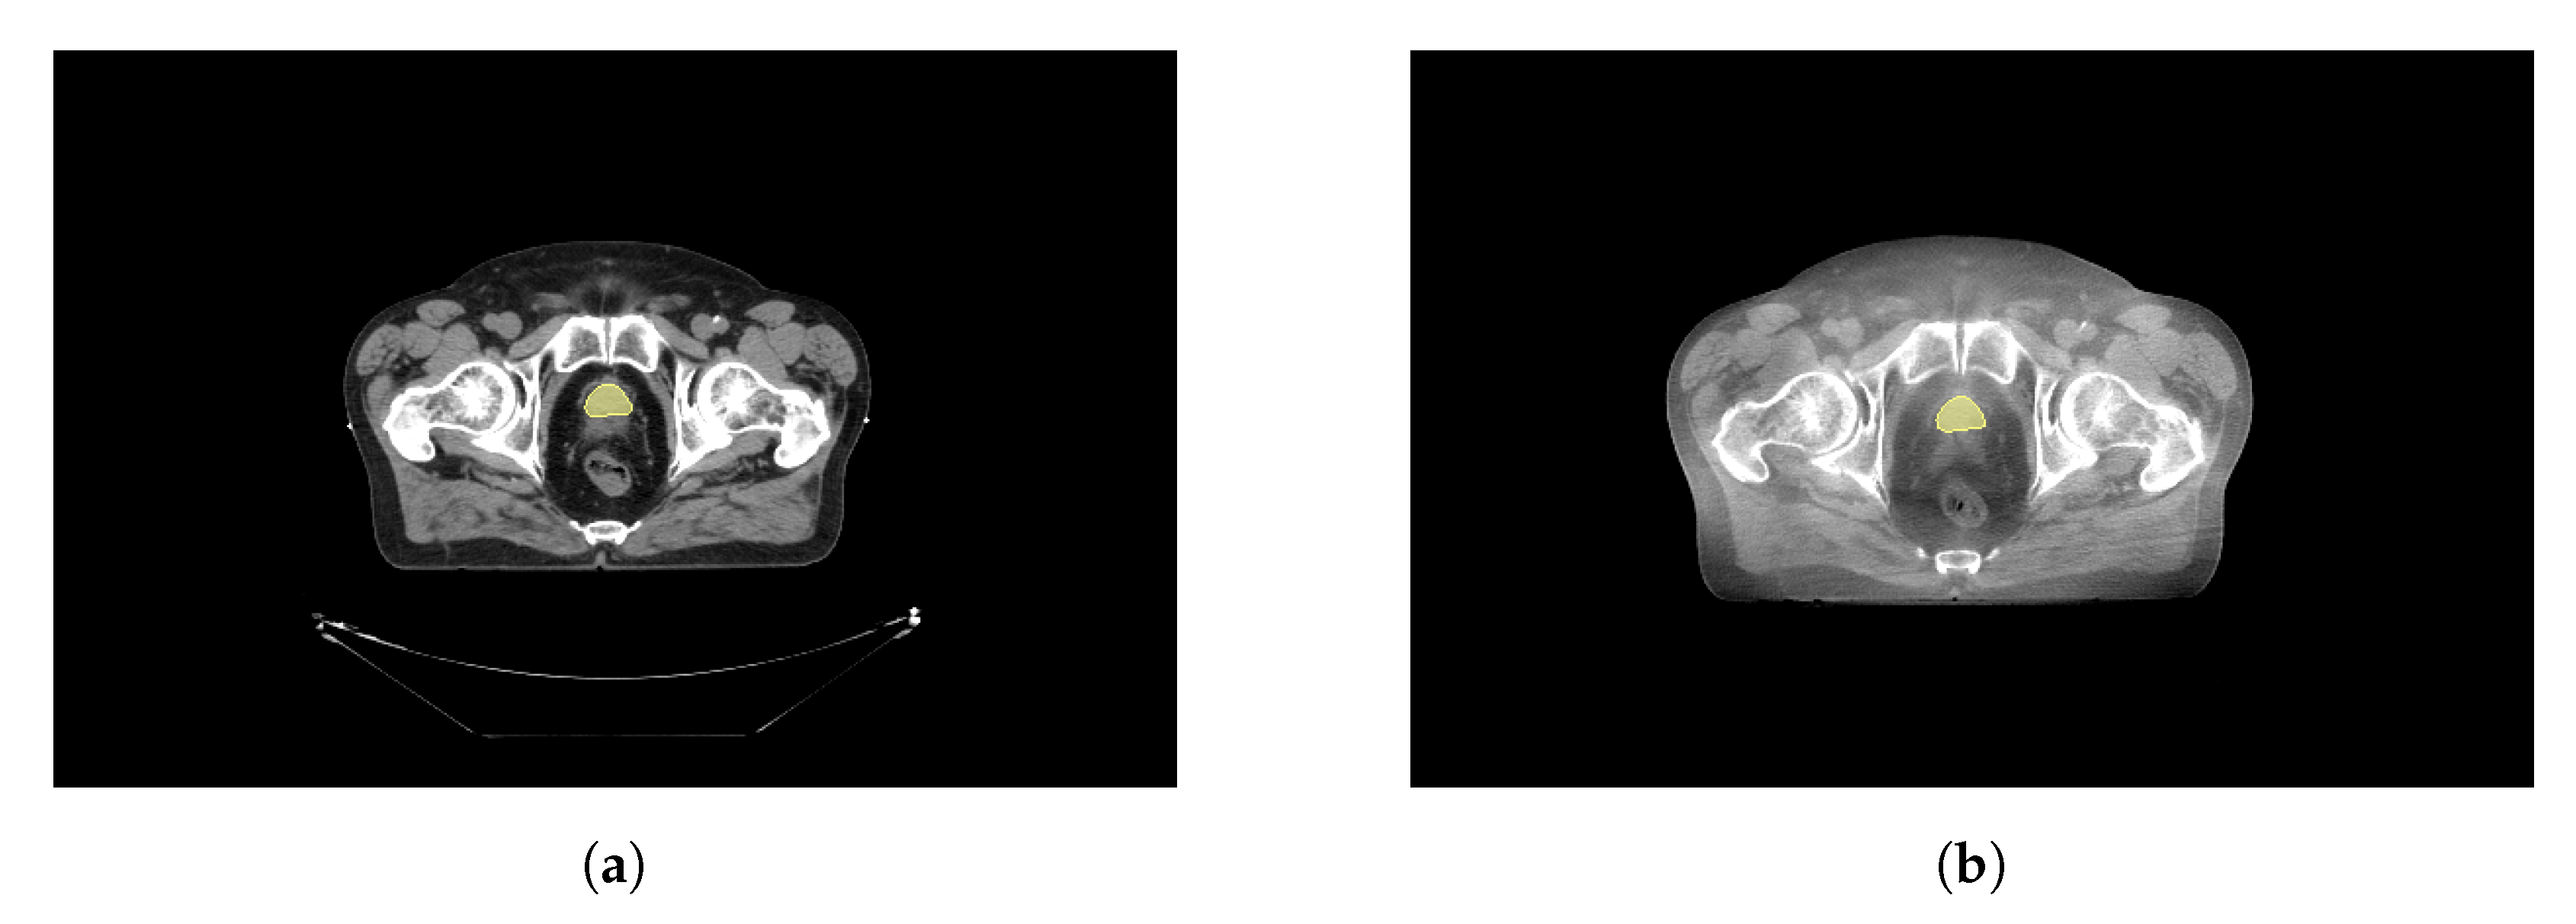

To transpose the structures defined in the CT to the CBCT, an elastic registration was performed using the Elastix toolbox [29,30] available as an extension from 3DSlicer [31]. The fixed volume was the CT, while the moving volume was the CBCT. The extension computed the displacement field which is then applied to the CBCT to transform the volume. Figure 2a shows an example CT image, and Figure 2b the registered CBCT and the manually defined CTV structure on both.

Figure 2. Initial CT scan with manually drawn prostate (yellow) and registered CBCT. (a) Initial CT scan. (b) First EBRT session CBCT.